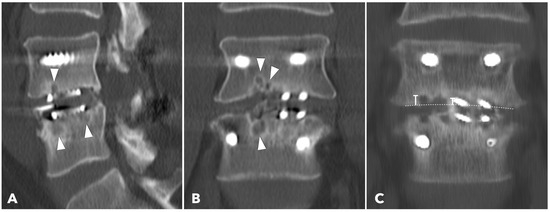

Improved Clinical and Radiological Outcomes with Double-Cage Biportal Endoscopic Transforaminal Lumbar Interbody Fusion: A Comparative CT-Based Study

by Yu-Hao Huang and Jwo-Luen Pao

Diagnostics 2025, 15(20), 2652; https://doi.org/10.3390/diagnostics15202652 - 21 Oct 2025

Cited by 1 | Viewed by 1504

Abstract

Background/Objectives: When transitioning from an older surgical technique to a newer one, we expect improved treatment outcomes and fewer complications. However, direct comparative studies to confirm these advantages are often lacking. Tubular minimally invasive transforaminal lumbar interbody fusion (MISTLIF) has been widely [...] Read more.

Background/Objectives: When transitioning from an older surgical technique to a newer one, we expect improved treatment outcomes and fewer complications. However, direct comparative studies to confirm these advantages are often lacking. Tubular minimally invasive transforaminal lumbar interbody fusion (MISTLIF) has been widely used, but limitations in visualization and endplate preparation may compromise fusion quality. Biportal endoscopic TLIF (BETLIF), a more recent alternative, offers enhanced magnification and superior hemostasis. Still, CT-based comparative data on fusion integrity remain limited. To evaluate the clinical and radiological outcomes following a chronological transition from MISTLIF to BETLIF, using thin-slice CT to assess fusion integrity. Methods: This retrospective study analyzed 179 patients treated by a single surgeon between January 2018 and May 2021. The first 90 cases underwent MISTLIF, followed by 89 BETLIF procedures. Clinical outcomes included Visual Analog Scale (VAS), Oswestry Disability Index (ODI), and Japanese Orthopedic Association (JOA) scores. Radiological assessments at one year postoperatively (X-ray and thin-slice CT) included disc height, segmental lordosis, Bridwell fusion grade, cage subsidence, and subchondral osteolysis. Results: BETLIF was associated with significantly shorter hospital stays (5.7 vs. 7.4 days) and fewer transfusions (0% vs. 14.7%). BETLIF showed significantly better ODI (12.7 vs. 23.5), JOA scores (26.4 vs. 20.6), and comparable VAS improvement. Radiologically, BETLIF had significantly higher fusion rates (93.3% vs. 82.4%), greater disc height restoration, and lower rates of cage subsidence (5.0% vs. 13.7%) and osteolysis (13.3% vs. 52.9%). Conclusions: BETLIF demonstrated superior clinical and radiological outcomes, likely due to enhanced endoscopic visualization and precise endplate preparation. Full article

(This article belongs to the Special Issue Diagnosis and Management of Spinal Diseases)

Show Figures

Figure 1